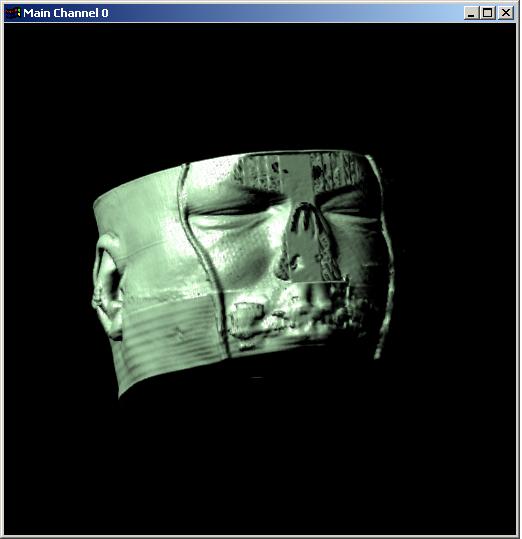

Visible human male CT data

Data

Resolution : 256x256x128

Visible human male CT data

Skin only

Data Resolution : 256x256x128

The following 12

images was generated by PC which has NVIDIA's GeForce3 GPU graphics card. The

hardware accelerated rendering techniques are used to make the following images.

To use the GeForce3 hardware, we have to use the OpenGL extensions like

GL_NV_texture_shader2, GL_NV_register_combiners, GL_EXT_texture3D,

GL_EXT_paletted_texture, GL_ARB_multitexture and so on. Since the GeForce3 card

allows the 3D texture shading, the image quality is better than the pixel of

frame buffer based shading in showing two materials at the same time.